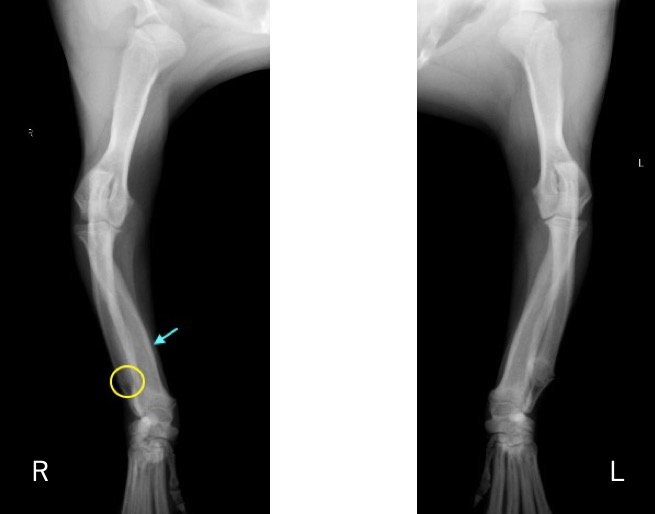

単純X線画像検査において、右側の尺骨遠位成長板領域の不透過性亢進、橈骨の頭側湾曲、鈎状突起と上腕骨顆の間隙が広がっている所見が認められたため、尺骨遠位成長板早期閉鎖が疑われました。

前腕のLateral像 (黄丸;尺骨遠位成長板の不透過性亢進 青矢印:橈骨の湾曲 赤矢印:鈎状突起と上腕骨顆の間隙)

前腕のAP像 (黄丸:尺骨遠位成長板の不透過性亢進 青矢印:橈骨の湾曲)